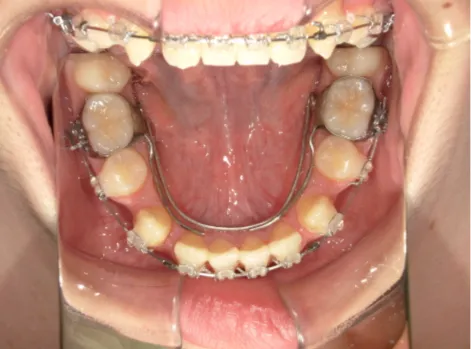

治療中⑧高1:15y11m 抜歯治療中

治療中⑨高2:17y1m 抜歯治療中

治療後⑩高2:17y7m 抜歯治療終了